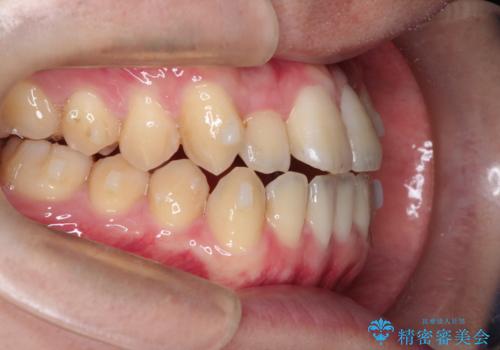

前歯のデコボコ インビザラインによる目立たない矯正

- 前歯のデコボコを主訴に来院された患者様です。

目立たないそうちをご希望されたので、インビザラインにて治療することとしました。

歯と歯の間をわずかに削ってスペースをつくり、デコボコを改善しました。